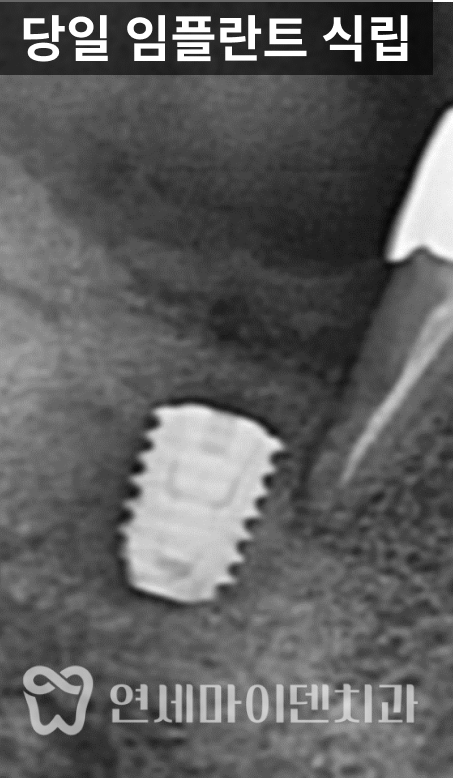

저희 병원에 재치료를 받으러 오신 사례입니다.기존 임플란트 실패 원인 분석

이 환자분은 한 달 전에 타원에서

임플란트를 식립 받으셨지만,불과 한 달만에 임플란트가 빠져서

저희 병원을 찾아오셨습니다.구강 내 상태를 확인하고

CT 촬영을 진행한 결과,

해당 부위는 골밀도가 낮았고

염증이 완전히 해소되지 않은 상태였습니다.또한 기존에 시행된

뼈이식 재료 역시

안정적으로 정착되지 못한 모습이

확인되었습니다.이러한 상황이라면

처음부터 발치 즉시 임플란트를

진행하기보다는,감염 부위를 충분히 제거하고

치조골 회복을 유도한 뒤

안정적인 환경에서 식립을 고려했어야 합니다.

또 하나 주목할 점은

픽스처 위에 힐링 어버트먼트가

이미 연결된 상태였다는 점입니다.고정력이 충분히 확보되지 않은 상태에서

힐링 어버트먼트를 연결하면

픽스처에 지속적인 힘이 전달되고,

이로 인해 임플란트 실패로

이어질 가능성이 높아집니다.실제로 이 케이스에서는

픽스처가 단단히 고정되지 않은 상태였고,

결과적으로 식립 후

한 달 만에 임플란트가 탈락하게 되었습니다.임플란트 재수술 과정

각별히 주의했습니다.남아 있는 건강한 치조골을 기반으로

새로운 픽스처를

보다 안정적으로 고정할 수 있도록

식립 위치를 재조정했습니다.

동시에 추가적인 뼈이식과

잇몸 치료를 병행하여

1차 수술을 당일에 마무리할 수 있었습니다.치유 과정과 최종 보철